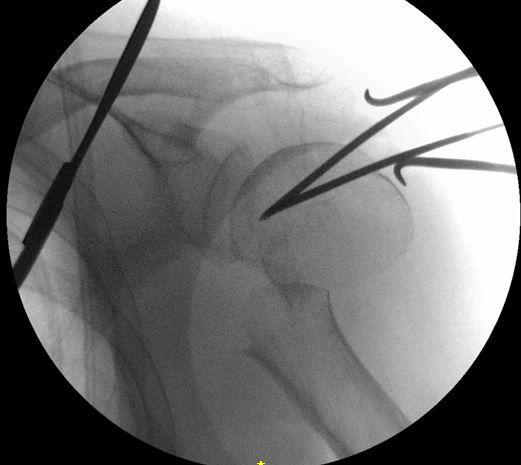

髄内釘のエントリーポイントを至適にするためには、転位した上腕骨頭を整復する必要があります。私は2.4 K-wireを肩峰外側から上腕骨頭に2本刺入して、これをjoy-stickにして整復します。

まず、1本目の2.4 K-wireを肩峰下に沿ってできるだけ上腕骨頭内側に進めます。この際、どうしても肩峰の外側が邪魔になるのですが、ある程度仕方ありません。

1本目の2.4 K-wireをできるだけ上腕骨頭内側に刺入して、これをjoy-stickにして整復します。しかし1本では整復力が弱いので2本目を刺入して、更に強力に整復を行います。

2本のK-wireをjoy-stickにして思いっきり整復します。上腕骨頭を内転位に保ちながら、上腕骨頭の頂点からガイドワイヤーを刺入します。

K-wireで上腕骨頭を内転位に整復位を保っておかないと腱板に牽引されて外転転位してしまい、髄内釘のエントリーポイントがかなり大結節寄りになってしまいます。